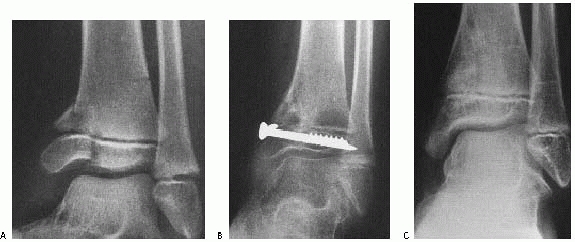

![]() |

FIGURE 26-39 A. Supination-inversion injury with a Salter-Harris type III fracture of the medial malleolus. B. Six months after open reduction and internal fixation with two transepiphyseal cannulated screws. C. Eighteen months after injury, the fracture has healed with no evidence of growth arrest or angular deformity. (Arrows note normal, symmetric Park-Harris growth arrest line.)

supplemented by a cast.

within the epiphysis, parallel to the physis, and should avoid the physis and ankle joint if possible (Fig. 26-38).